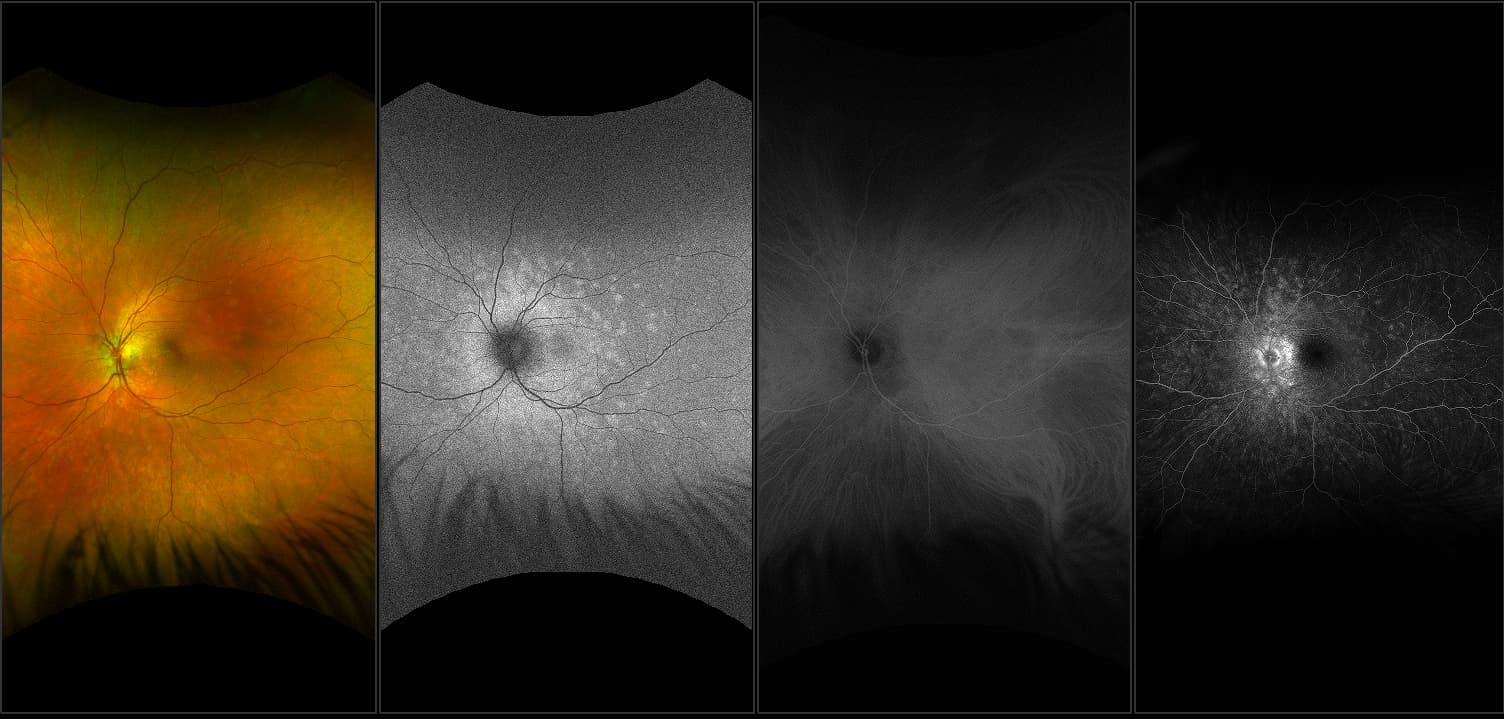

California - Large Pars Plana Cysts - Steered, RG

Pars plana cysts are a common peripheral retinal pathology that do not raise much clinical concern. They do not affect the central vision and observation alone is typically recommended. Pars plana cysts are something to be considered when peripheral retinal elevation is noted on routine exam.